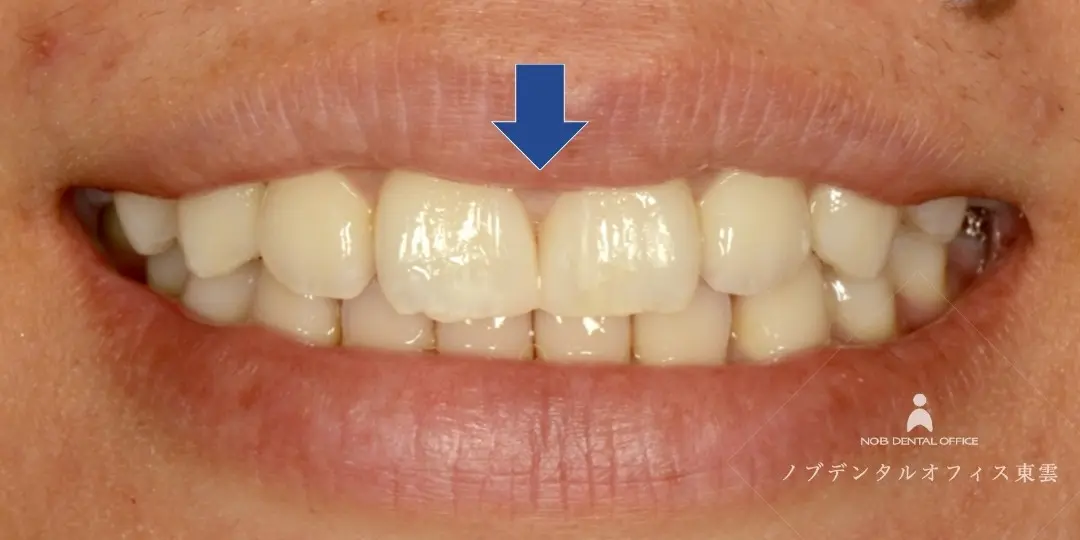

すきっ歯をコンポジットレジンで治した症例(20代女性)

「前歯のすき間が気になる」「笑った時の見た目をきれいにしたい」とご来院されました。

コンポジットレジンで修復することで、1日で治療が完了しました。

前歯の形態とバランスを整えました。

| 費用 | コンポジットレジン 55,000円(税込) 保険適応外 |

| リスク | ・経年的に摩耗が起こることがあります。 ・噛みしめや歯ぎしりにより、欠けたり外れる可能性があります。 ・清掃状態や生活習慣によ っては境目から虫歯や歯周病が起こることがあります。 |